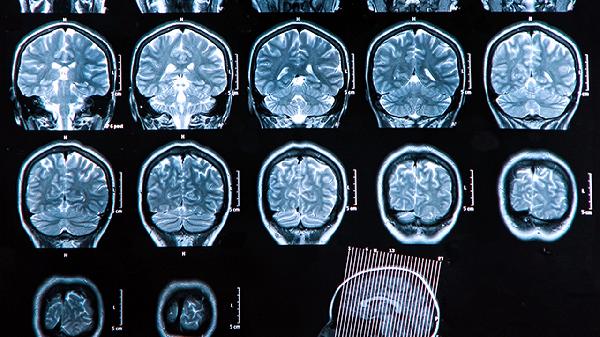

大脑双侧额顶叶脑萎缩的症状有哪些

大脑双侧额顶叶脑萎缩的症状主要有记忆力减退、执行功能障碍、性格改变、语言能力下降、运动协调异常等。额顶叶是大脑负责高级认知功能的关键区域,其萎缩可能导致多种神经功能障碍。

建议出现上述症状时尽早就诊神经内科,通过头颅MRI等检查明确萎缩程度。日常生活中可进行认知刺激活动如阅读、拼图,保持适度社交。饮食注意增加深海鱼类、坚果等富含ω-3脂肪酸的食物,避免高盐高脂饮食。规律进行太极拳、散步等温和运动,有助于维持神经功能。家属需给予充分理解支持,避免指责患者的行为改变,必要时寻求专业护理指导。